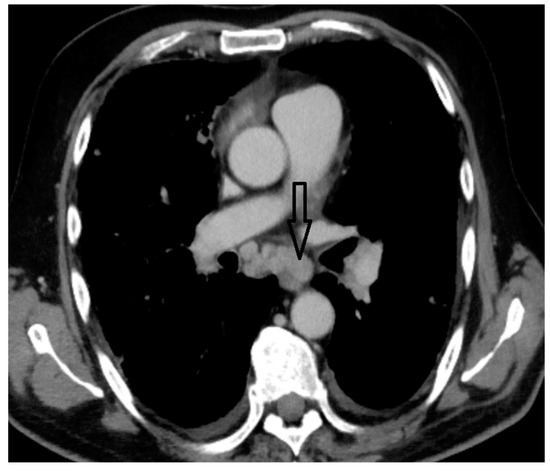

2. Case Report